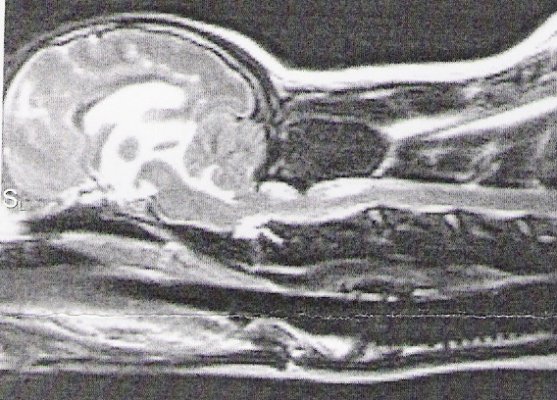

Above is shown a comparison of an MRI showing a full cerebellum

vs. the skull X-RAY of a dog with a full cerebellum and a dog

with an MRI showing a crushed cerebellum vs. the skull X-RAY of

a dog with a crushed cerebellum. The cerebellum is circled in

red. You can easily see there is a huge difference in shape of

cerebellum between these two dogs--the one on the left is quite

full, the one on the right is severely crushed.

The skull x-ray of a dog with a full cerebellum is below that on

the left and the skull x-ray of a dog with a crushed cerebellum

is shown on the right. You can easily see there is a distinct

difference in the shape of the back of the skull between the two

and why the cerebellum ends up crushed. The most distinct

difference, besides the fact that the skull on the right is

shorter from front to back, is that the occiput sticks out in

the skull x-ray on the left. In the right, that occiput is still

there, but it is more downsloped and blends in with the back of

the skull to the point you can barely see it--almost like

someone took a hammer to the occiput and smashed it in.